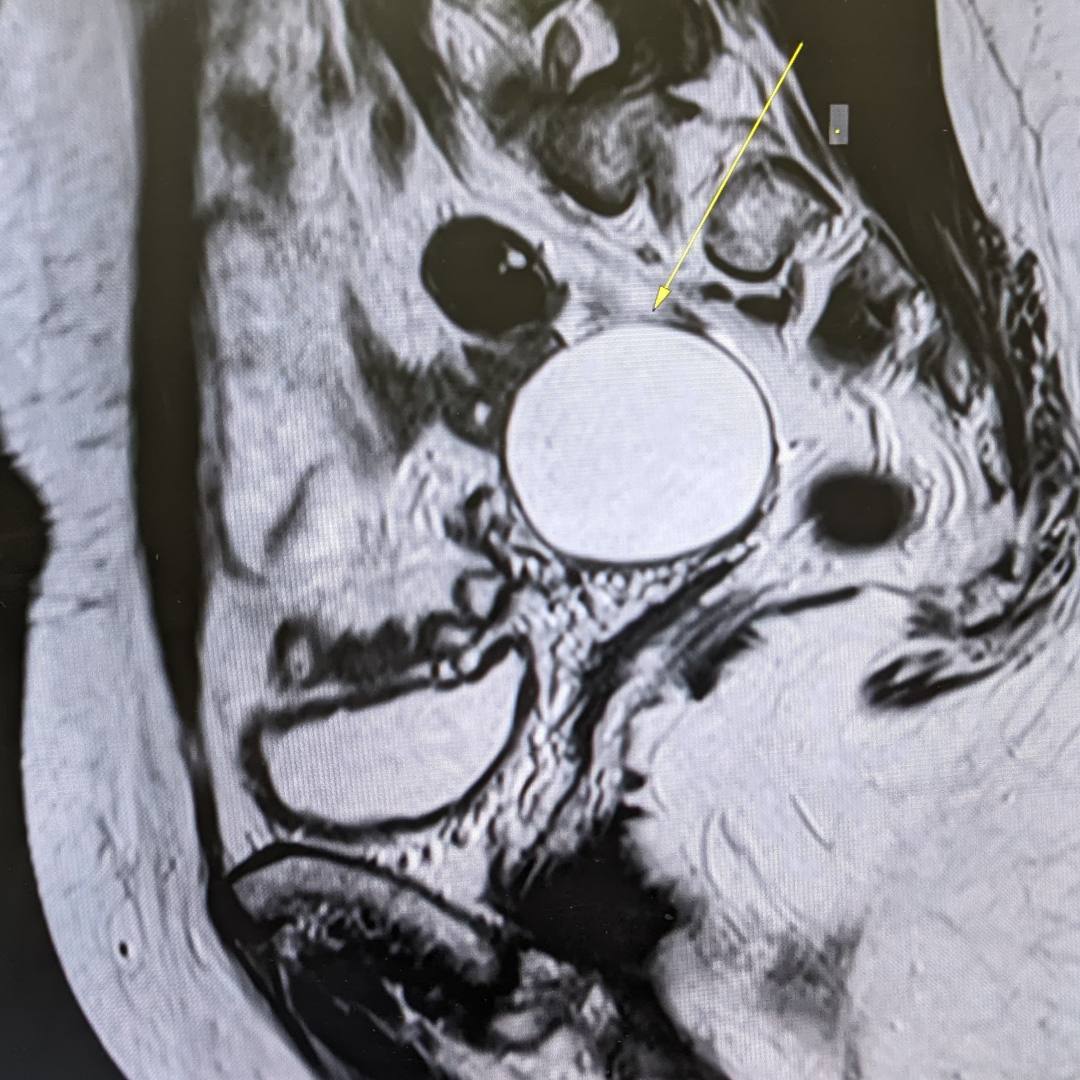

53-летняя пациентка обратилась к гинекологу в рамках программы check-up. При осмотре документации выяснилось, что на проведенных УЗИ-исследованиях от 2021 и 2023 года определяется образование правого яичника, требующее дифференциальной диагностики между эндометриоидной кистой и кистозно измененным яичником.

С целью оценки образования, уточнения его структуры и динамики роста пациентке было проведено МРТ органов малого таза.

При МРТ было выявлено жидкостное кистозное образование правого яичника без папиллярных разрастаний, гораздо больших размеров относительно первоначального УЗИ-исследования.

Учитывая анамнез пациентки, особенности структуры и размеры образования, была заподозрена цистаденома.

Пациентка направлена на повторную консультацию к гинекологу с последующим удалением данного образования, учитывая отрицательную динамику роста.